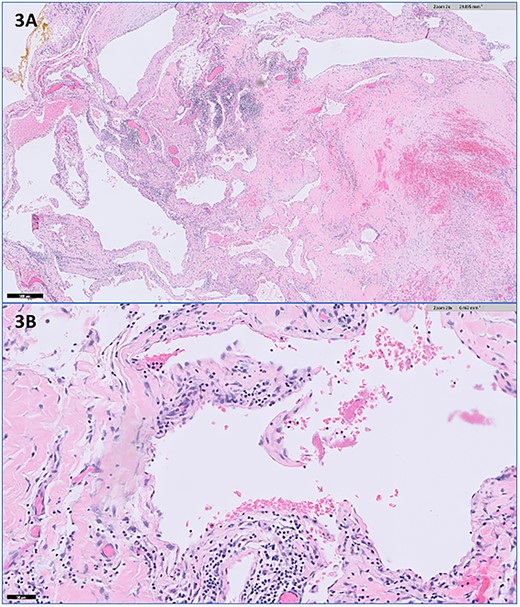

A 33-year-old premenopausal female presented with concern for accessory breast tissue in her left axilla (Fig. 1A). The area was enlarging after her recent pregnancy and with current breastfeeding. It became increasingly tender. She had no prior history of breast disease, breast biopsies or hormone replacement. She was previously on birth control. On exam, the patient had a prominent area of tissue involving her left axilla, measuring 9 × 10 cm. There was no erythema, induration, dimpling or lymphadenopathy. An ultrasound (US) demonstrated a complex cystic mass in the left axilla, measuring 9.7 × 8.2 × 6.5 cm. The cyst was aspirated after core needle biopsy was unsuccessful, yielding 225 ml of serosanguinous fluid with some remaining internal debris. No malignant cells were present on fluid analysis. The patient returned the next day with worsening pain and firmness to her left axilla. There was now concern for bleeding into cyst cavity after aspiration. An additional aspiration was performed with another 140 ml of sanguinous fluid obtained and subsequent cyst collapse. Again, the swelling and pain recurred overnight. A repeat US showed a slightly increased avascular collection (11.6 × 9.5 × 6.7 cm), now with internal echos (previously anechoic and simple), and a central nodular area concerning for clot. A computed tomography of the chest again demonstrated the complex cystic axillary mass (9.9 × 7.7 × 8.7 cm) with a central retracted clot, no active contrast extravasation and the left axillary artery posteriorly. The patient’s pain continued to worsen, now extending into her back and neck. On exam, the swelling had increased into the upper outer quadrant of the left breast. The patient was admitted to the hospital for drainage by interventional radiology. Hemoglobin was unremarkable. A 10 French drain was placed, and 180 ml of dark blood was collected. Cultures were negative. The patient had relief of her symptoms the next day. One week later, the patient underwent excision of left axillary cystic mass and new drain placement. The mass was surrounded by small vessels and extended superior to the left axillary vein. It measured >10 cm once excised (Figs 2A and B). The final pathology identified it as a vascular malformation, likely a hemangioma versus an arteriovenous malformation (Fig. 3). The patient had an uneventful post-operative course with drain removal 10 days later. No further fullness or swelling was reported.

Representative histopathologic images of the vascular malformation with hematoxylin and eosin stain showing ectatic vessels with luminal red blood cells and lined by flattened endothelial cells at (A) 2× magnification and (B) 20× magnification.